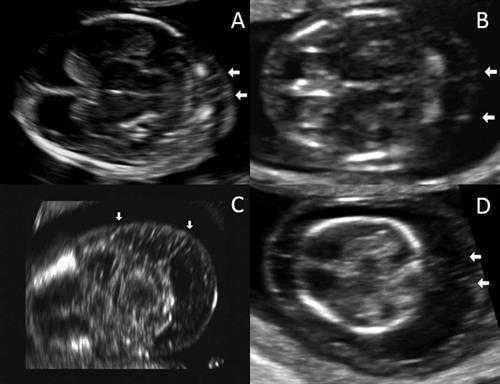

УЗ изображения воротниковых перегородок в поперечном срезе. А) воротниковое пространство 2.3 мм. В) 4 мм. С) 5.2мм. D) 8мм. Все изображение предоставлены the Journal of Ultrasound in Medicine.

Эти результаты демонстрируют, что визуализация септ воротникового пространства в первом триместре является важным и независимым фактором риска хромосомных аномалий плода, по данным группы исследователей.

Исследователи ретроспективно просмотрели электронные истории болезни 3275 пациенток, которые проходили скрининг первого триместра и затем рожали в женском отделении Техасского Детского Госпиталя между ноябрем 2011 и декабрем 2014 года. Они характеризовали септы как тонкие линейные эхогенные структуры в воротниковом пространстве плода, которые располагались между кожей плода и нижерасположенными тканями. Кроме того, наличие септ и расширенного воротникового пространства расценивалось как кистозная гигрома.